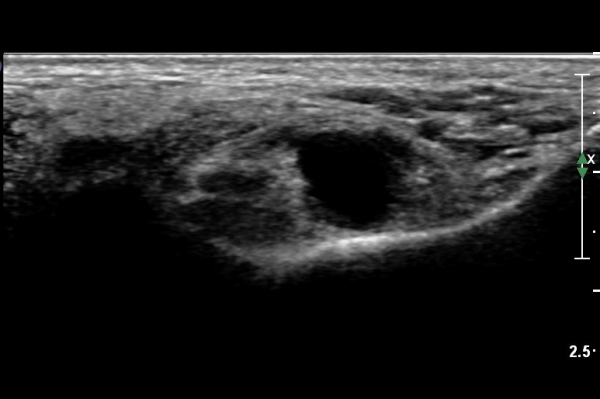

ŽÃËÀÚ¸¦ Á¶±Ý ´õ ¸»´ÜÀ¸·Î À̵¿ÇÏ´Ï Á¶±Ý¸¸ ³¶Á¾ÀÌ µÎ ½Å°æ »çÀÌ¿¡¼­ °üÂûµÈ´Ù(»çÁø 3).